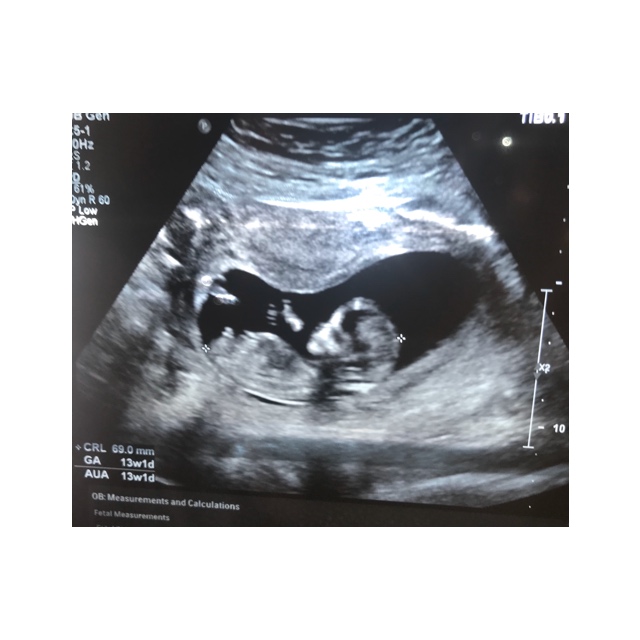

I just had my 12 week scan yesterday. I was 12 weeks 4 days but baby was measuring 13 weeks 1 day.

I didn’t get many good photos & I’m not even sure if the nub is pictured. I’d love any guesses that you might have :)

Attachment 42166Attachment 42167Attachment 42168